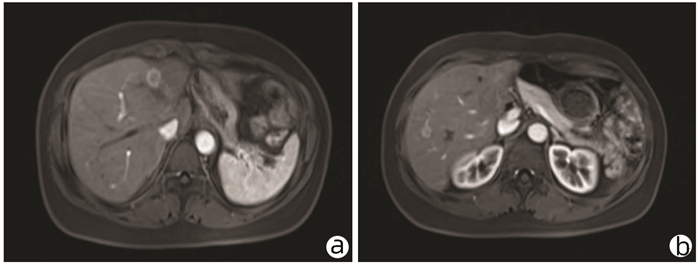

食管胃静脉曲张内镜下治疗后并发可逆性后部脑病综合征1例报告

于亭亭, 姜珊珊, 朱萌然, 白云

2022, 38(1): 177-179. DOI: 10.3969/j.issn.1001-5256.2022.01.030

摘要(816) HTML (198) PDF (3069KB)(57)

摘要: